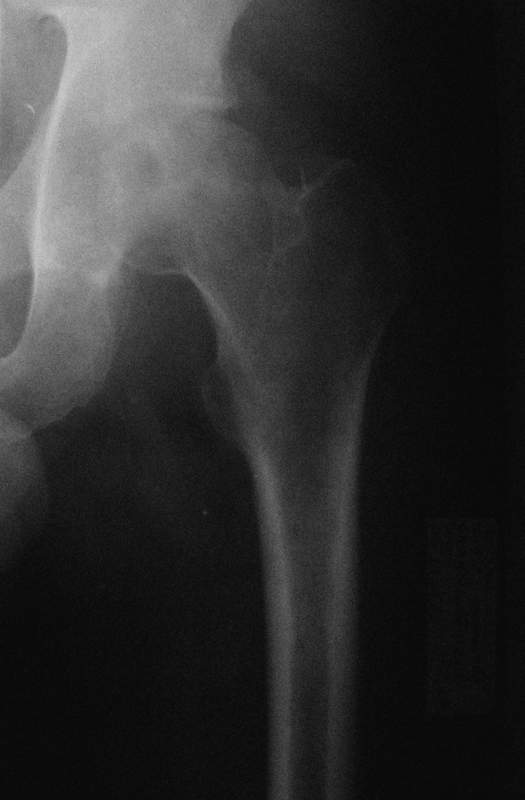

Молодой человек, 37л. Начало заболевания сентябрь 2007, резкие боли в области лев. тазобедренного сустава, повышение температуры до 39 гр., в течение недели, лабораторные данные: лейкоцитоз со сдвигом влево. Посев крови на стерильность возбудителя не выявил. По данным Рг, РКТ выставлен диагноз: Левосторонний коксит? Асептический некроз? Проводилось лечение: цефсон в/в неделю, иммобилизация кокситной повязкой 1 мес. Обратился повторно 10 дней назад с жалобами на сильные боли в левом тазобедренном суставе, белая кровь – нормограмма, СОЭ 46 мм/ч. На сегодняшний день: болей не отмечает. Лаб.данные: белая кровь – нормограмма, СОЭ 30 мм/ч. Рентген и РКТ прилагаем.

Рассмотреная тактика лечения: операционная биопсия.

При отрицательных данных за коксит - диагноз асептический некроз - эндопротезирование

При положительных данных за коксит какие методы могут быть использованы?